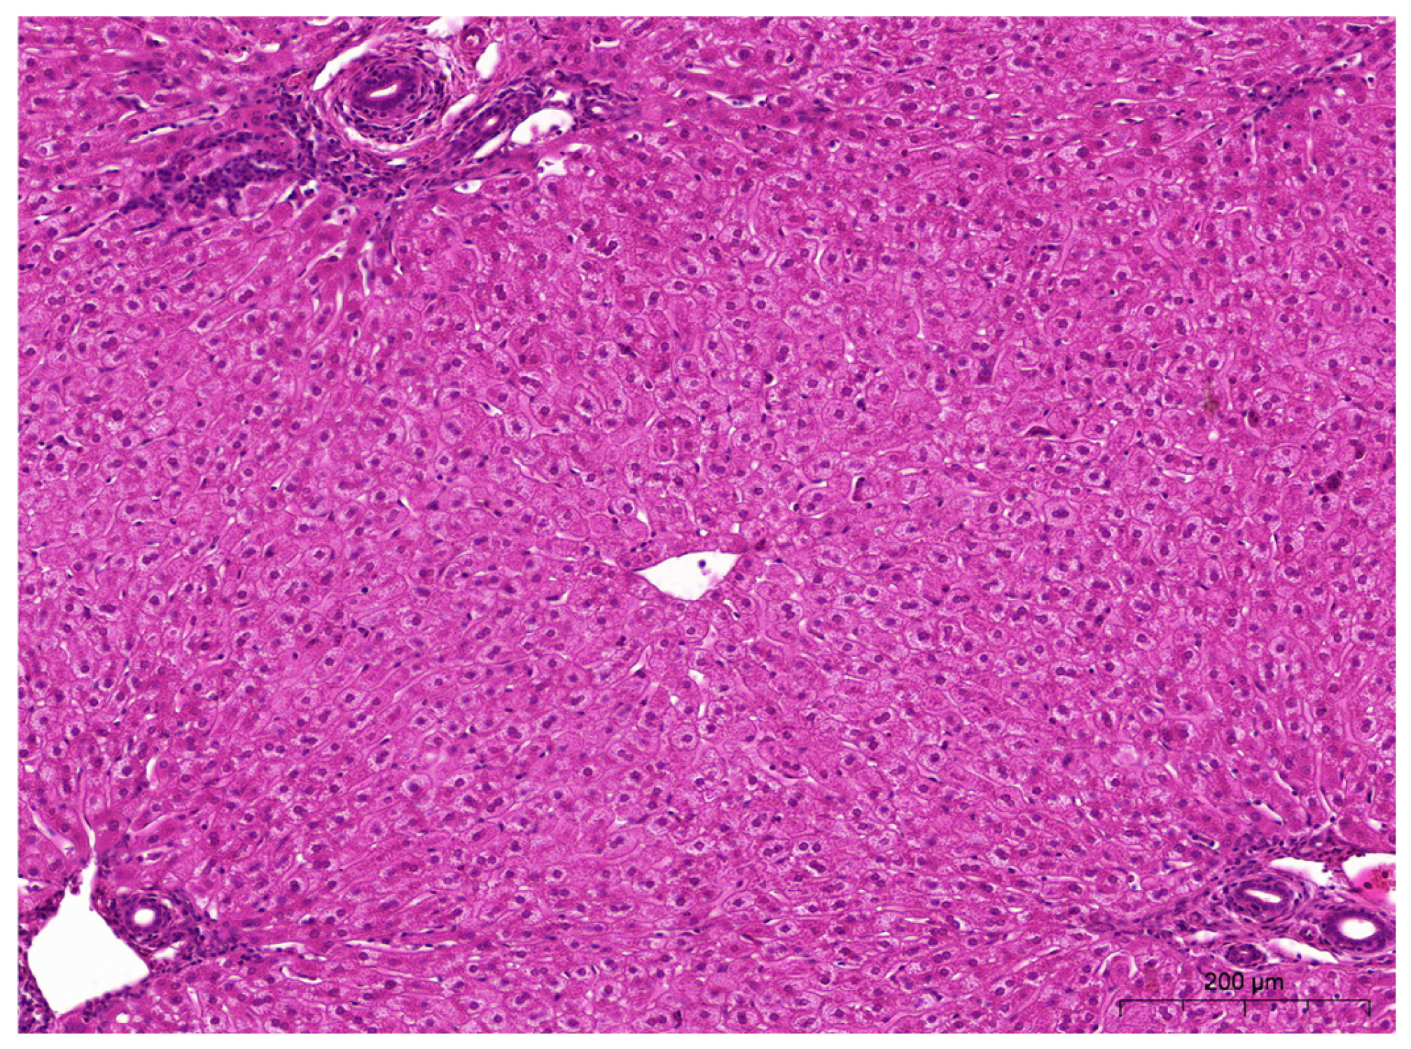

2.5. Histopathological Examinations of the Liver and Kidneys